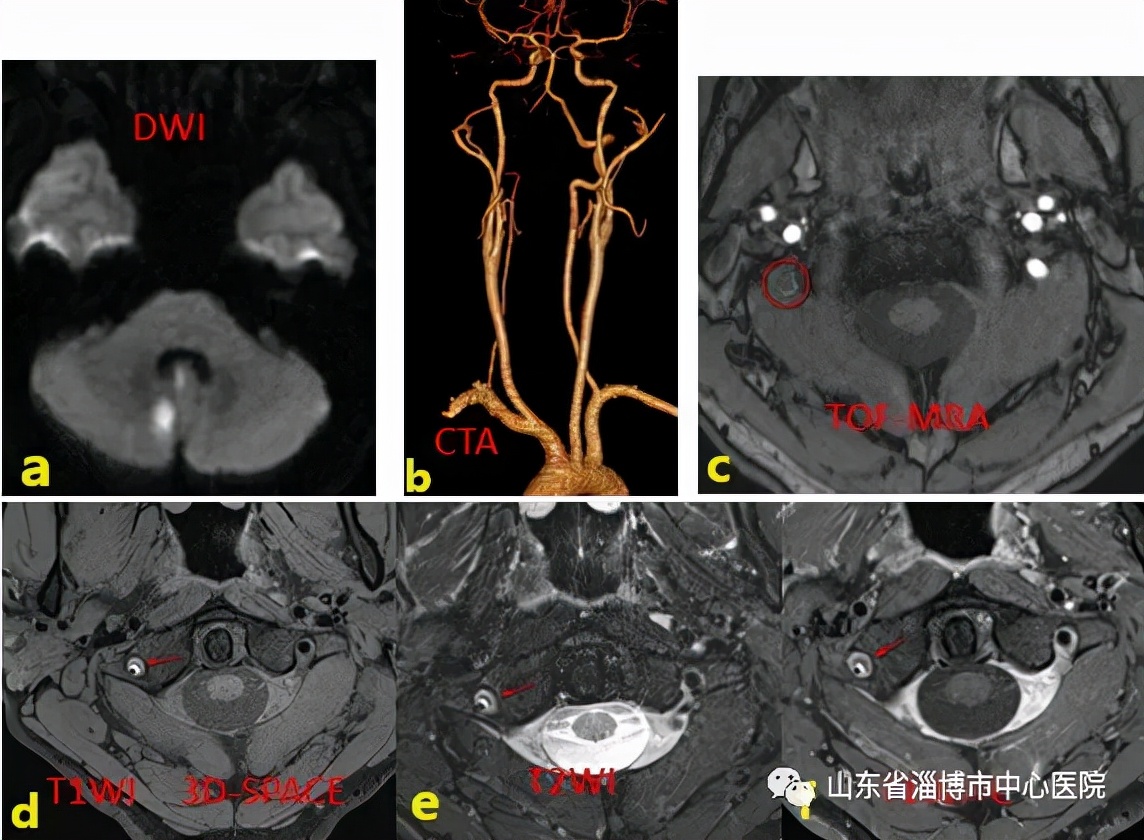

患者25岁,有颈椎按摩史,头晕头痛半天,入院诊断突发小脑梗死。

图示a:DWI序列示小脑新发脑梗死;b:头颈部CTA示右侧椎动脉远段未显影;c:MRA示右侧椎动脉远段未见显影;d:高分辨T1像显示双腔征;e:T2序列显示双腔征,内膜片;f:增强扫描假腔未见明显强化。综合诊断为右侧椎动脉夹层。

VW-MRI可显示颅内动脉的管壁特征,分析粥样硬化斑块的成分和稳定性,是否易损斑块,有助于卒中病因分型及明确发病机制。在其他血管疾病诊断中也有非常大的应用价值。在血管炎病人中,管壁多为向心性增厚及均匀强化,并可对血管炎活动性进行评估。VW-MRI能清晰显示双腔征、内膜片及壁内血肿等动脉夹层的直接征象。可逆性脑血管收缩综合征病人的管壁一般无强化或轻度强化。而对于动脉瘤的患者,瘤璧无增强提示动脉瘤稳定,有强化则提示破裂风险增加。